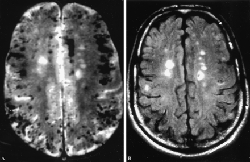

small-vessel-ischemia-brain-mriOver time, though, as small vessel ischemia recurs, eventually clusters of damage occur in the brain. This disrupts the normal neurological pathways of how information is learned and communicated. One of the most clear indicators of vascular dementia is difficulty in communication. One of these difficulties is misnaming things.